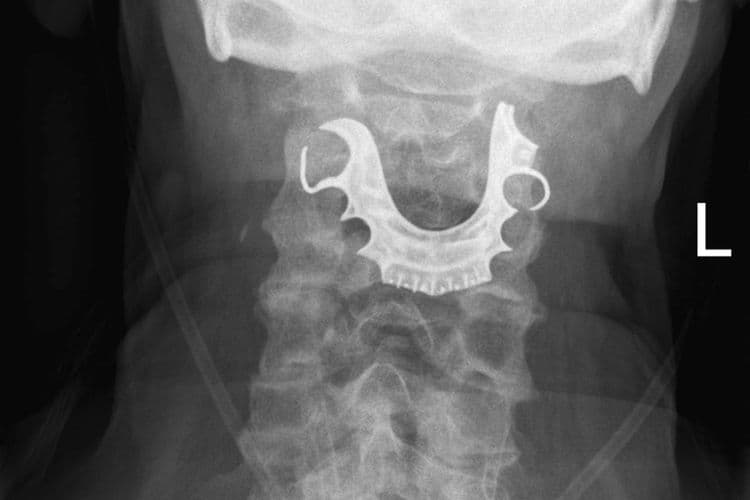

हे जेव्हा आजोबांना सांगण्यात आलं तेव्हा ते म्हणाले की माझी कवळी ऑपरेशनपासून हरवली आहे. हे समजताच त्यांच्या घशाचा एक्स-रे काढण्यात आला. यावेळच्या एक्स-रे मध्ये त्यांची हरवलेली कवळी त्याच्या घशात अडकल्याचं उघड झालं.

मंडळी, शस्त्रक्रियेच्या वेळी अनेस्थेशिया दिल्यानंतर त्यांची कवळी त्याच्या घशात पडली आणि त्यांने ती नकळत गिळली होती. आजोबांवर तातडीची शस्त्रक्रिया करण्यात आली. ६ दिवसानंतर त्यांना घरी सोडण्यात आलं.